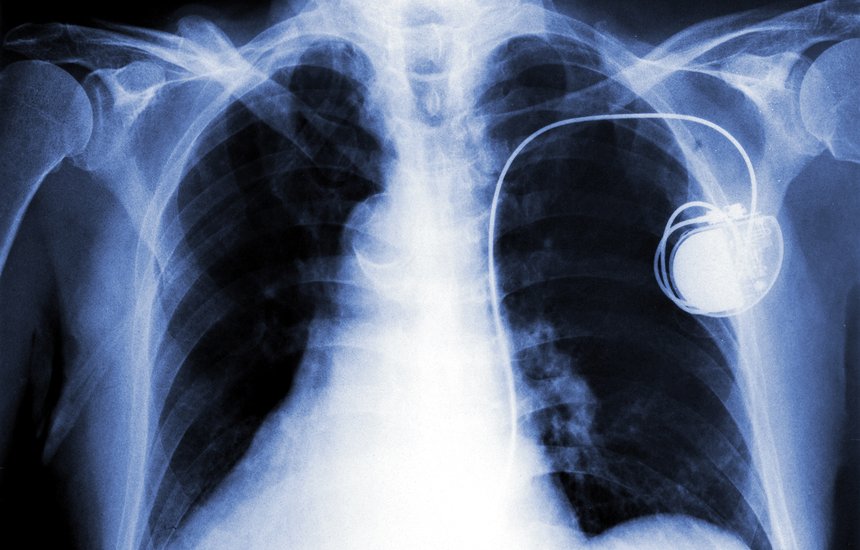

Так что киборгом можно считать любого человека, имеющего сложные и эффективные медицинские импланты, протезы и стимуляторы. Ученые успешно создают киборгов уже несколько десятилетий: более 50 лет назад был создан первый полностью находящийся под кожей электрокардиостимулятор — устройство, которое поддерживает частоту сердечных сокращений у больного. Сегодня электрокардиостимуляторами никого не удивить: ежегодно вживляется более 500 000 таких приборов.